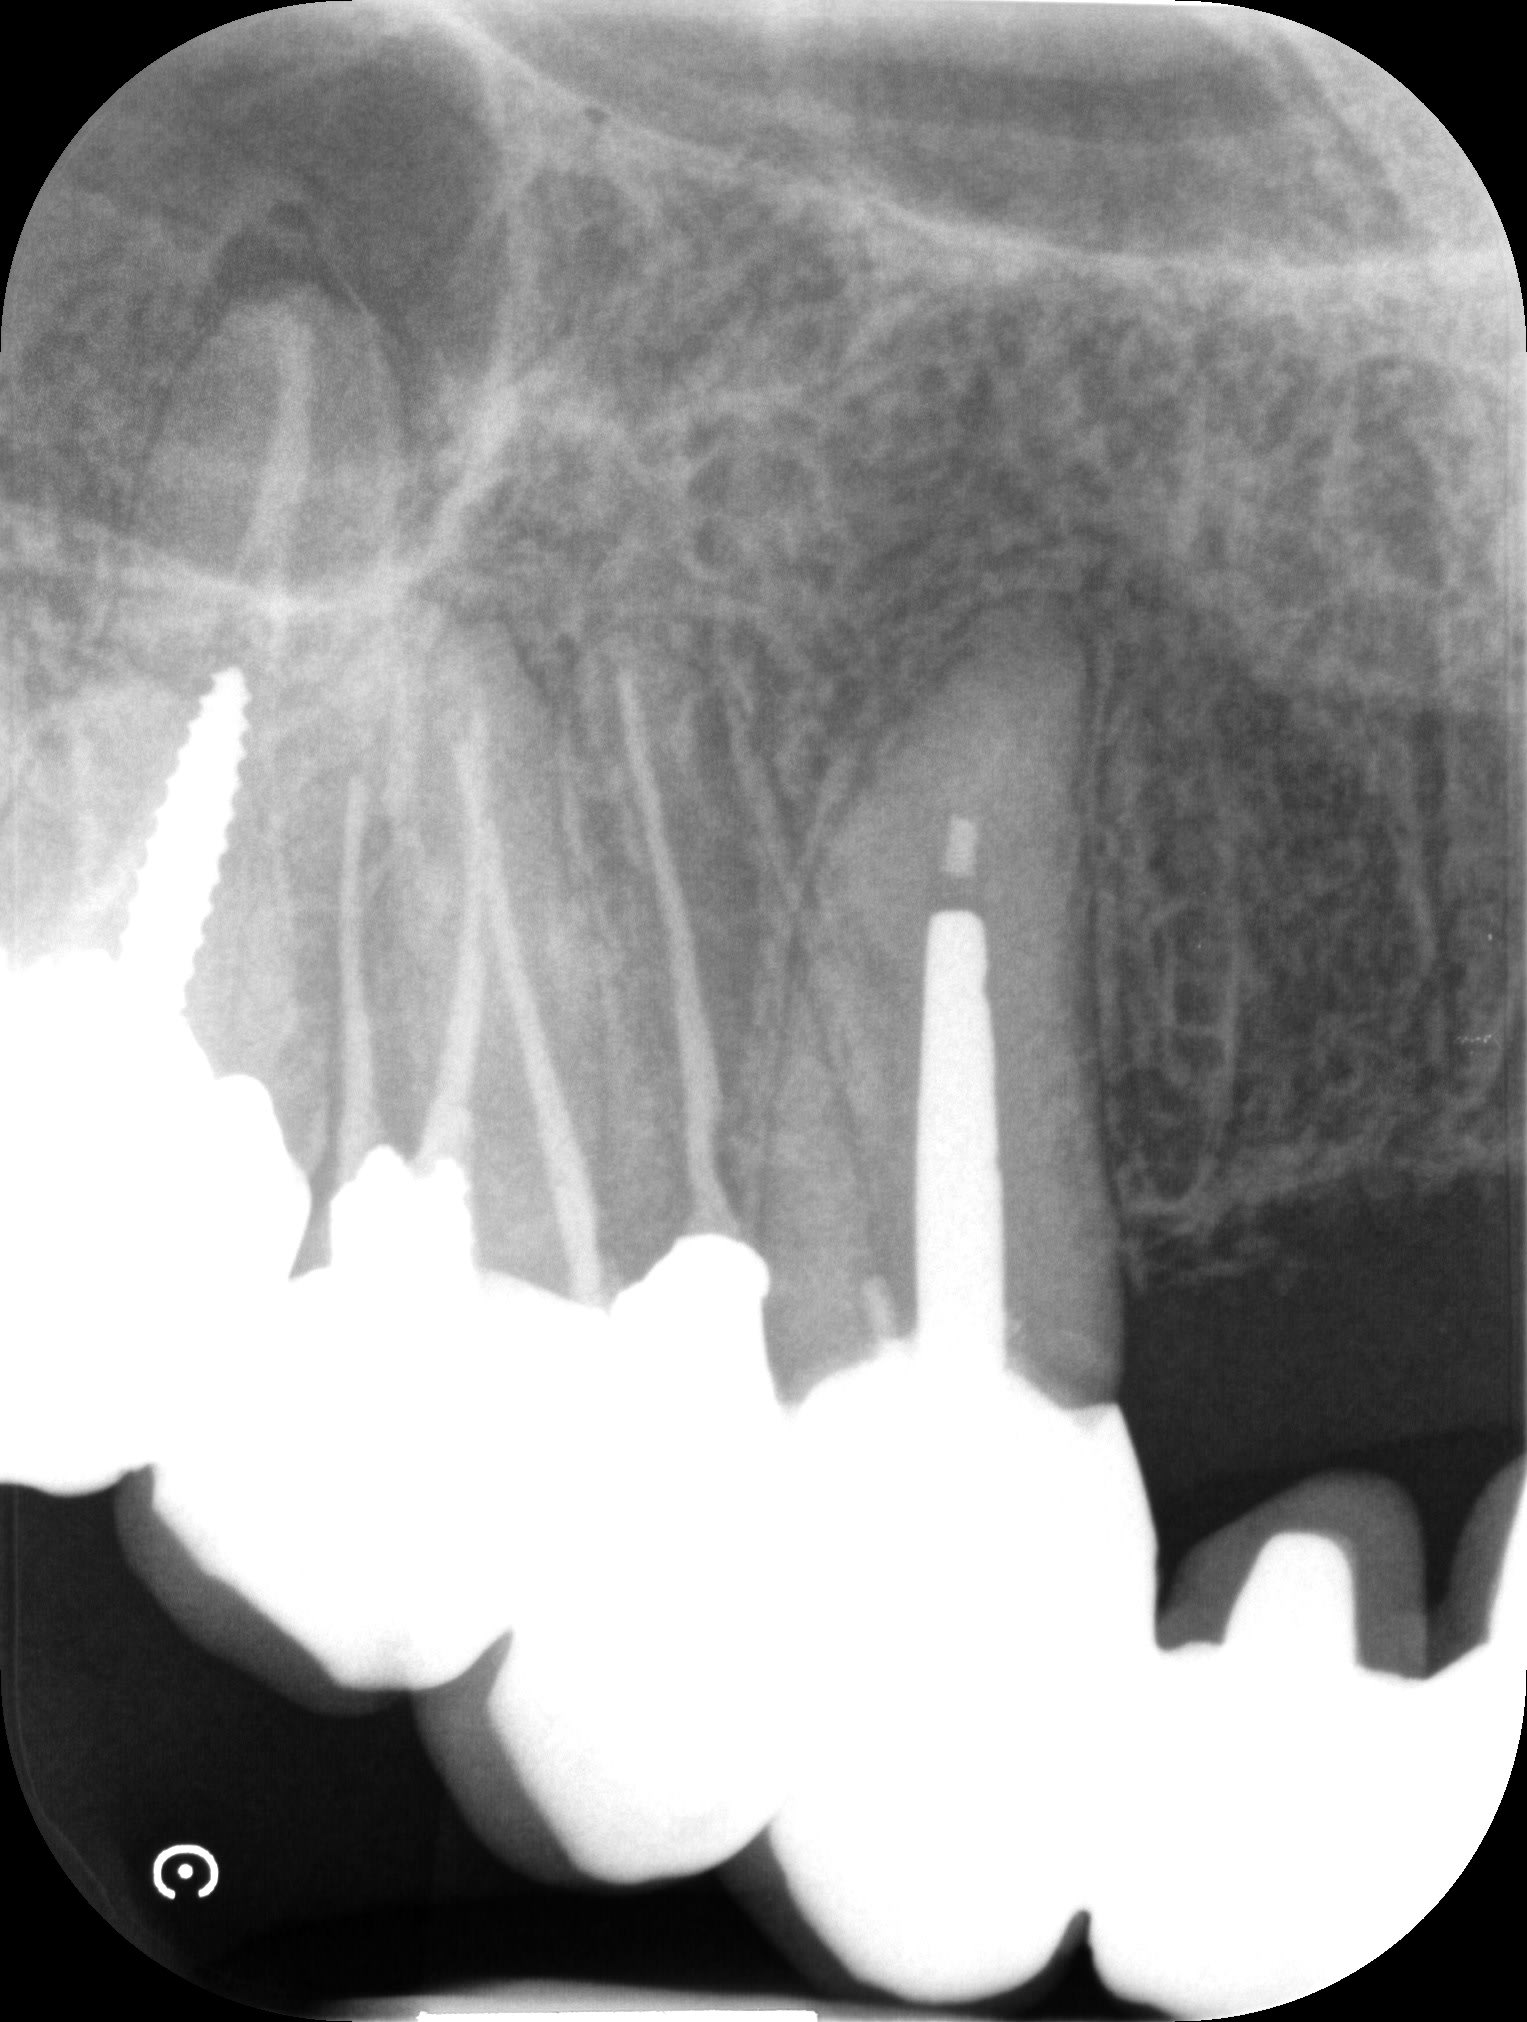

secteur 4, en 2005

secteur 3, en 2012

Pas de grande portée, mais ça tient, même si ça sent le sapin à droite